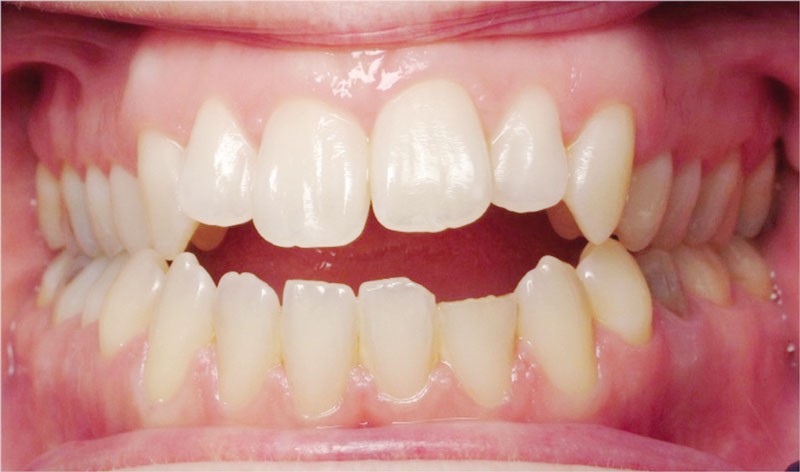

Cas n° 1

Il a été décidé de mettre en œuvre une thérapeutique avec brackets vestibulaires Damon afin d’optimiser l’expansion des arcades, la fermeture de la béance et la réduction du sourire gingival latéral qui perturbe l’esthétique du sourire de la patiente.

La patiente demande des attaches céramiques et nous trouvons un compromis en lui proposant un appareillage Insignia Damon Clear au maxillaire et Damon métallique à la mandibule.